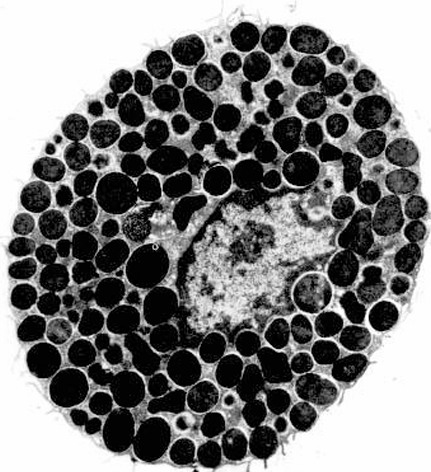

Basófilo

Mastocitos